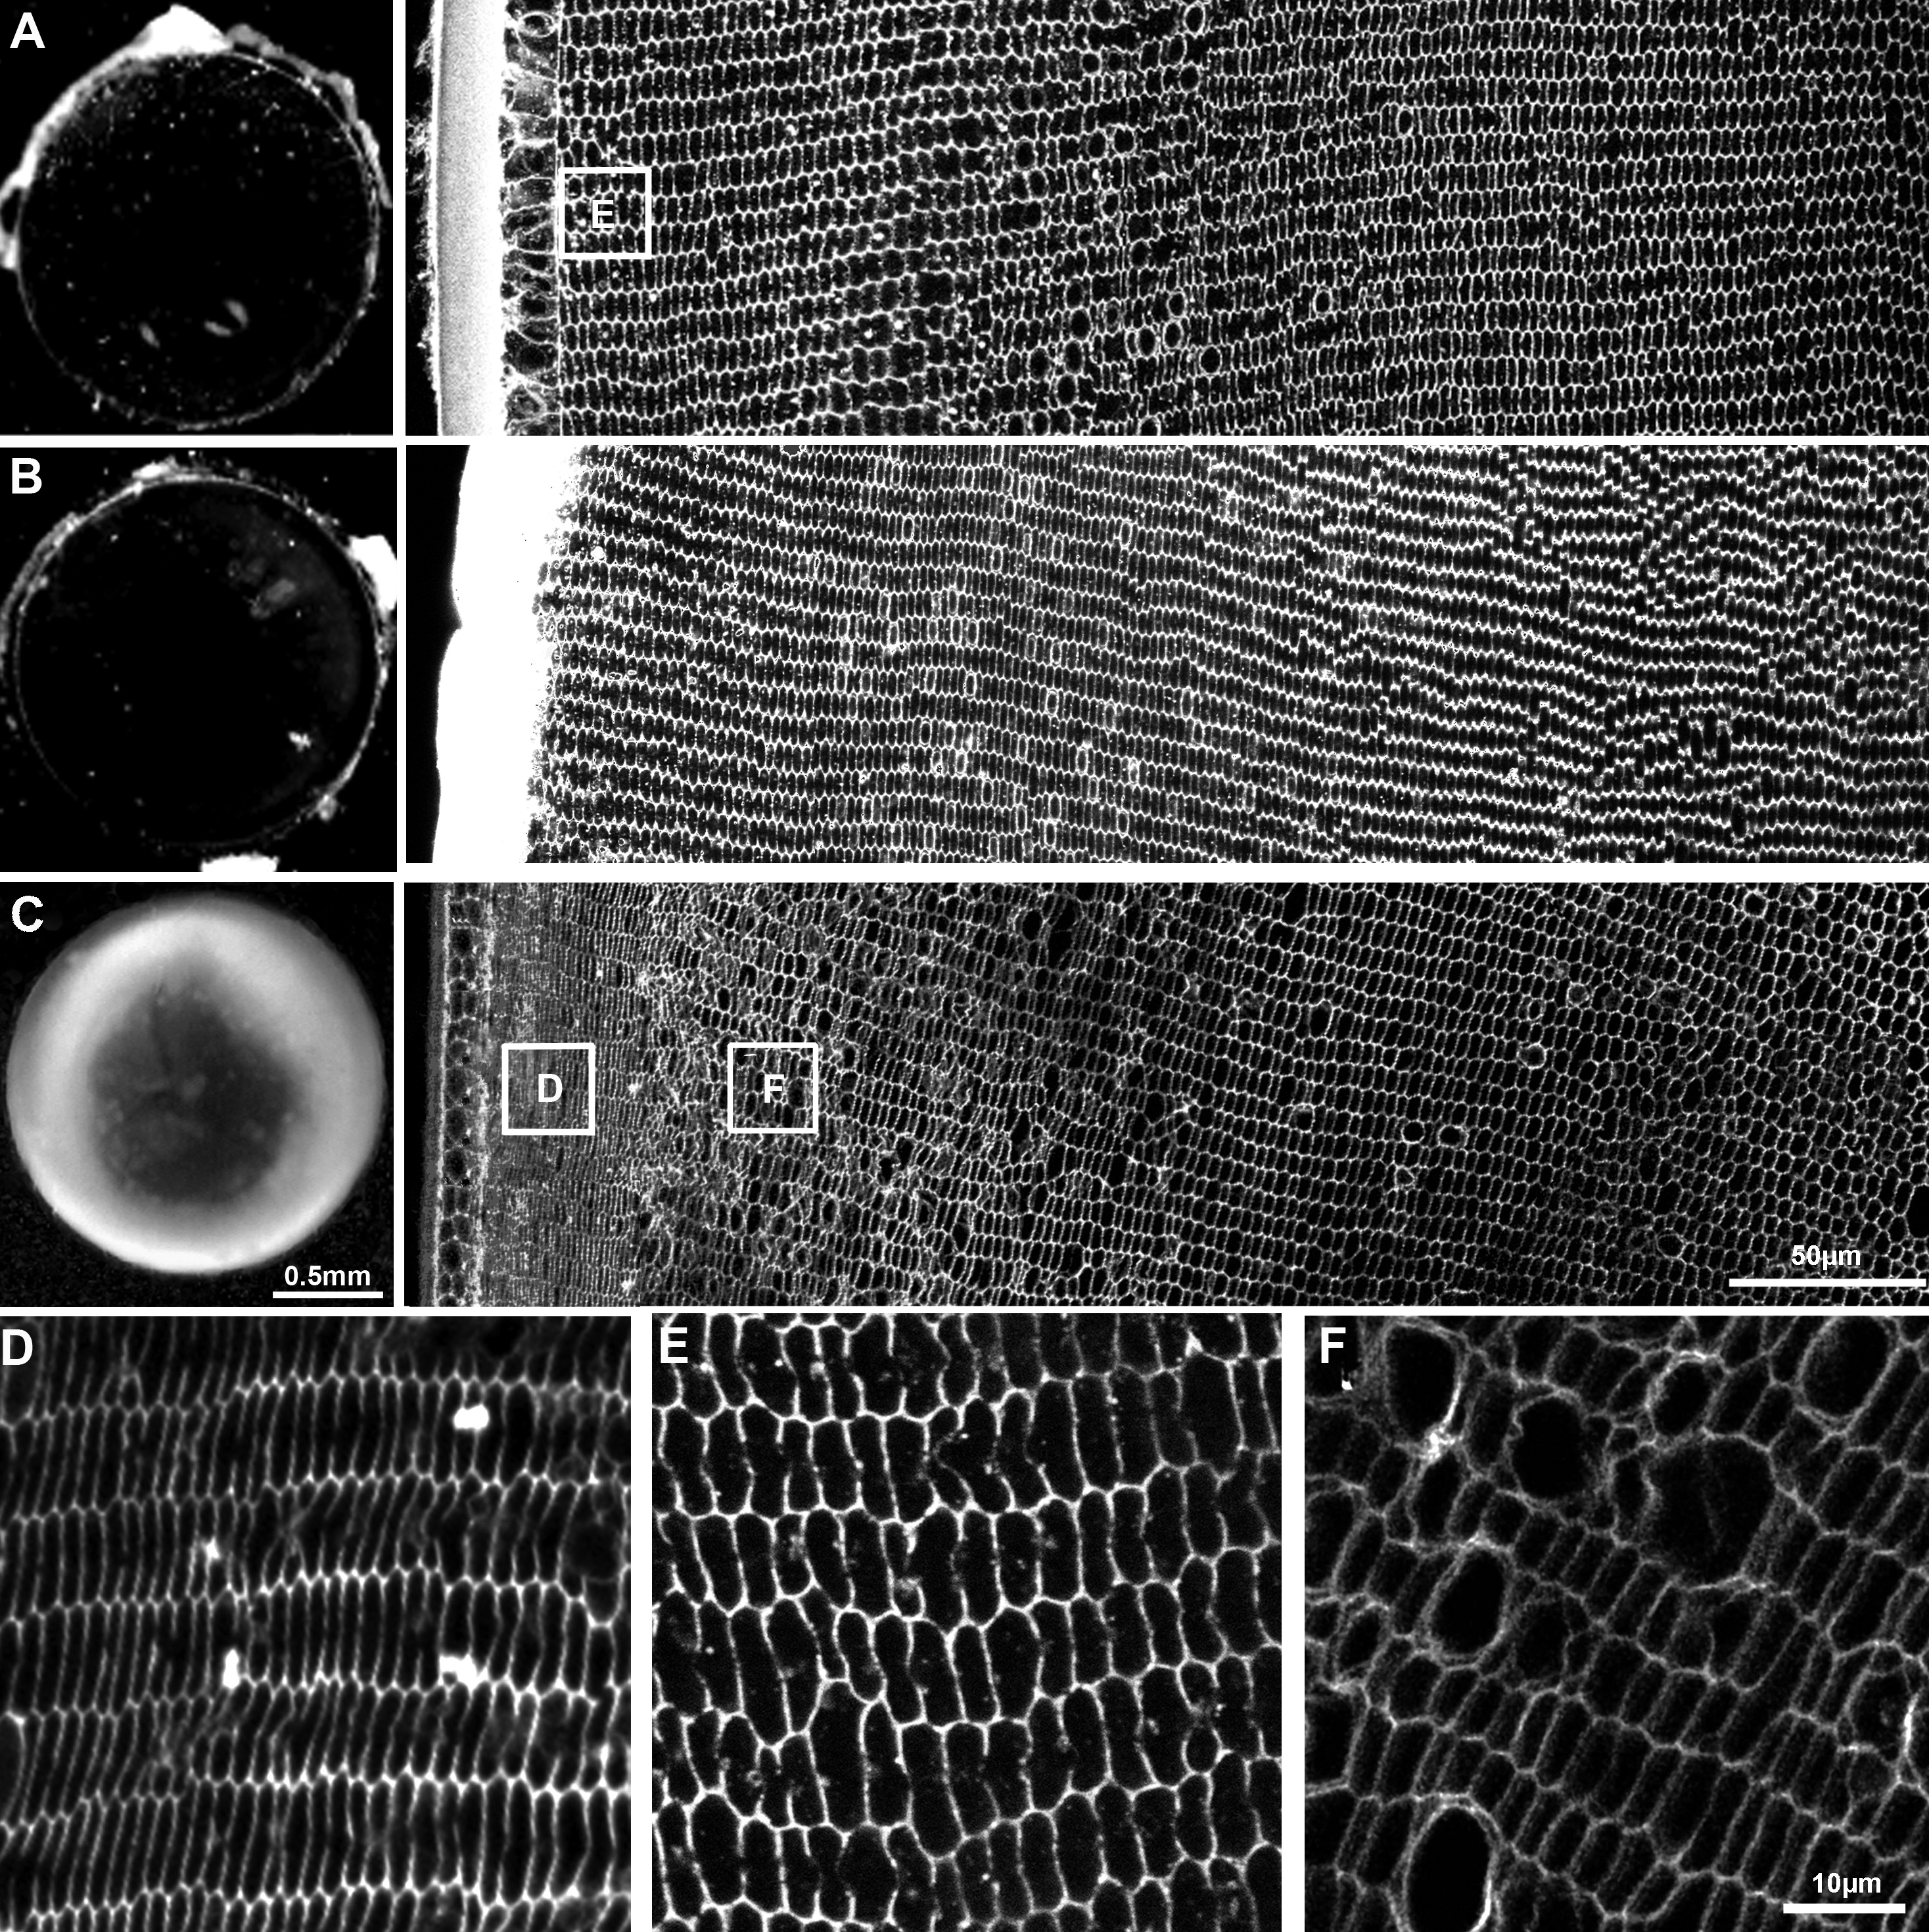

Figure 5. Effects of NCC and NKCC

inhibitors on lens transparency and fiber cell morphology. Rat lenses

were organ cultured for 18 h in isotonic AAH in either the absence (A)

or

presence of the NCC inhibitor thiazide (B) or the NKCC

inhibitor bumetanide (C). Lens transparency was monitored by

dark field microscopy while fiber cell morphology was determined by

imaging equatorial sections labeled with the membrane marker WGA.

Culturing lenses in AAH only (A) or AAH + 10 μM thiazide (B)

had

no major effects on lens transparency (left panels) or fiber cell

morphology (right panels). C: Culturing lenses in AAH + 2 μM

bumetanide caused cortical opacification of the lens (left panel) that

was induced by damage to cortical fiber cell morphology (right panel). D-F:

High

powered images from the areas indicated (boxes) in A and C.

Fiber

cells in the lens periphery exhibited a marked shrinkage in the

presence of bumetanide (D) relative to that observed in the

absence of the inhibitor (E), while in the deeper influx zone

dilations of the extracellular space between fiber cells (F) was

observed in the presence of bumetanide.